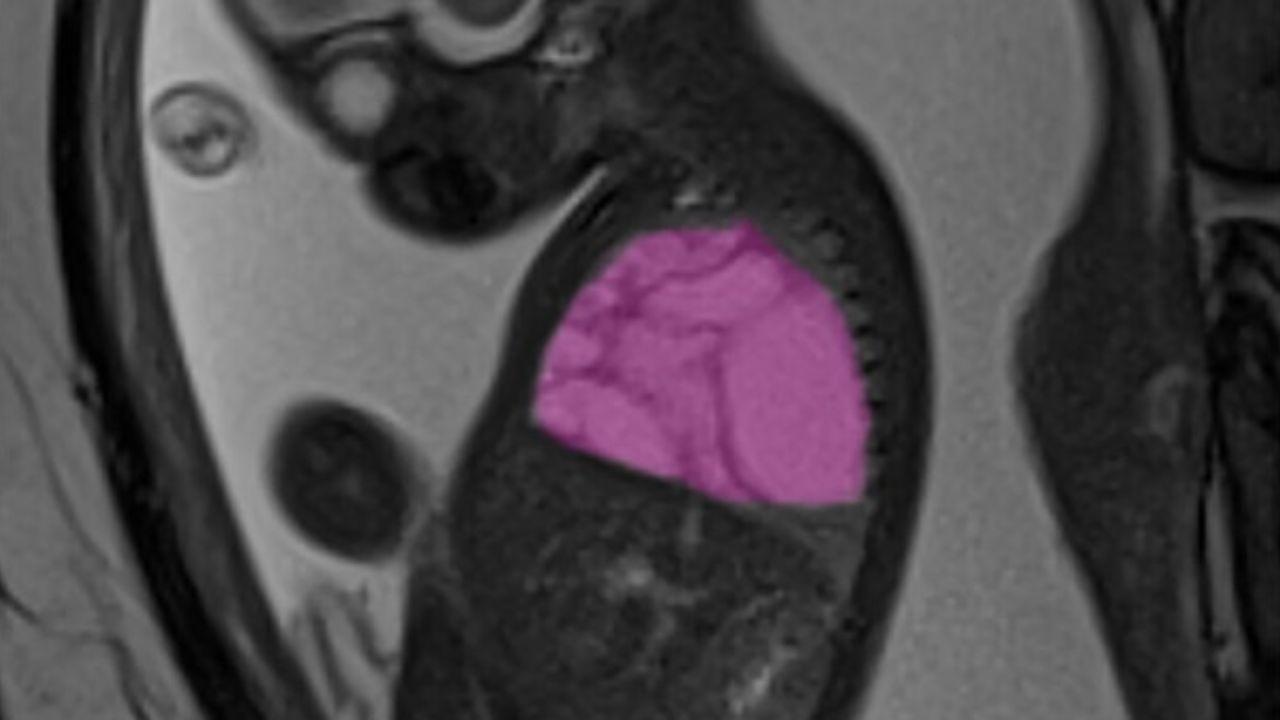

Durante la gravidanza, la diagnosi prenatale aveva rivelato una voluminosa cisti polmonare congenita di circa 9x6x5 centimetri (più grande di un’arancia), un volume tale da occupare quasi interamente la cavità toracica destra del feto e comprimere cuore e polmone di sinistra, con la conseguenza di un grave scompenso cardiaco fetale (idrope). Per risolvere la situazione ad alto rischio per la sopravvivenza del feto, alla 24a settimana di gravidanza, quando Alessandro era ancora nella pancia della mamma, i chirurghi fetali hanno eseguito il posizionamento di uno shunt pleuro-amniotico, un sottile drenaggio che mette in comunicazione il torace del feto con il liquido amniotico consentendo di ristabilire la normale funzione cardiaca. La procedura è stata realizzata presso l’ospedale San Pietro Fatebenefratelli, centro ostetrico di II livello, da un’équipe congiunta composta dagli specialisti ostetrici del San Pietro e dai chirurghi fetali del Bambino Gesù guidati dalla dott.ssa Isabella Fabietti, con il coordinamento del dott. Leonardo Caforio, responsabile di Ostetricia, Ginecologia e Diagnosi prenatale dell’Ospedale Pediatrico romano.

Alla 35a settimana di gestazione, infatti, Alessandro è nato al Bambino Gesù con un parto cesareo programmato, nell’ambito del percorso dedicato ai nascituri affetti da gravi patologie congenite. Subito dopo il parto, una volta stabilizzato dai neonatologi, il piccolo è stato sottoposto a indagini strumentali che hanno confermato la patologia del polmone destro. Il giorno successivo l’équipe dei chirurghi neonatali del Bambino Gesù ha eseguito una lobectomia toracoscopica, rimuovendo l’intero lobo inferiore del polmone destro con una tecnica mini-invasiva che prevede tre piccolissime incisioni. Il piano chirurgico e terapeutico per Alessandro e la sua mamma è stato realizzato grazie anche alla collaborazione con gli specialisti radiologi dell’Unità di Imaging Avanzato Cardio-toraco-vascolare e Fetale del Bambino Gesù, guidati dal dott. Aurelio Secinaro, che si sono occupati dello studio per immagini del caso (risonanza magnetica pre-natale e angio-TC post-natale) arricchito da ricostruzioni 3D. «La cisti era molto grande, occupava quasi tutto il torace del piccolo - racconta il dott. Andrea Conforti, responsabile dell’Unità di Chirurgia Fetale e Neonatale del Bambino Gesù - Dopo la nascita, lo abbiamo operato in toracoscopia, una procedura mini-invasiva che ha consentito un recupero rapido e senza complicanze. Oggi Alessandro respira con due lobi polmonari invece di tre, ma sta bene: i lobi sani si sono riespansi e compensano perfettamente la funzione respiratoria. Potrà avere una vita normale, anche praticare sport, in futuro». Commenta il dott. Leonardo Caforio: «Il nostro ospedale si trova spesso a gestire casi fetali complessi, nei quali le possibilità di successo dipendono strettamente dal lavoro combinato di diverse equipe di specialisti, tutti impegnati a garantire il benessere di due pazienti contemporaneamente, vale a dire la mamma e il nascituro. Grazie a questo tipo di organizzazione, che prevede anche la collaborazione con Centri esterni di eccellenza, il Bambino Gesù rappresenta oggi una realtà di riferimento nel centro-sud del Paese per la presa in carico e la cura dei piccoli pazienti con gravi patologie malformative congenite, ancor prima della nascita».